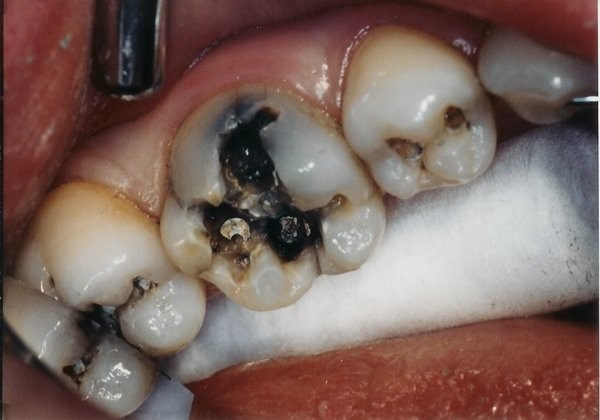

Sâu răng đen là tình trạng bệnh lý răng miệng phổ biến, xảy ra khi vi khuẩn tấn công và phá hủy cấu trúc mô cứng của răng (men răng và ngà răng) trong một thời gian dài. Biểu hiện đặc trưng nhất là sự xuất hiện của các đốm đen, vết nâu sẫm hoặc các lỗ khuyết lõm trên bề mặt răng.

- Giai đoạn 1 (Sâu men): Xuất hiện các đốm đen nhỏ hoặc các đường rãnh đen li ti trên mặt nhai. Lúc này men răng bắt đầu bị tổn thương nhưng thường chưa gây đau nhức.

- Giai đoạn 2 (Sâu ngà): Vi khuẩn tấn công vào ngà răng. Lỗ sâu to dần, thức ăn dễ bị giắt vào gây cảm giác ê buốt thường xuyên. Đây là “thời điểm vàng” để thực hiện trám răng thẩm mỹ nhằm bảo tồn răng thật.

- Giai đoạn 3 (Viêm tủy): Lỗ sâu ăn sâu vào buồng tủy, gây đau nhức buốt lên tận óc, đặc biệt là ban đêm. Bệnh nhân cần được điều trị tủy ngay để tránh áp xe xương hàm.